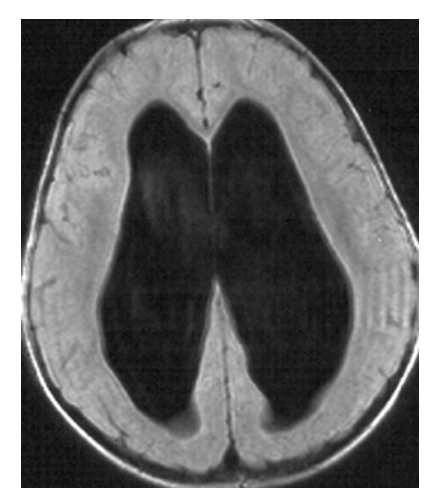

Hydrocephalus. T1-weighted axial MRI shows markedly dilated lateral ventricles with low-signal CSF.